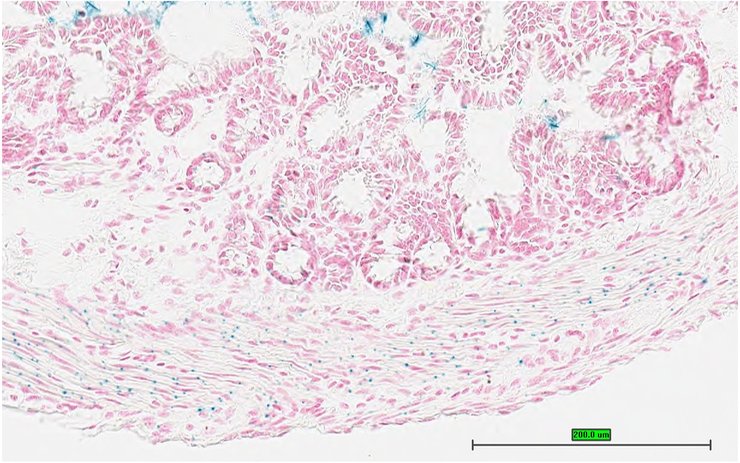

TS28: bladder Present UC Davis_1860100

TS28: bladder Present UC Davis_1860101

TS28: bladder Present UC Davis_1860125

TS28: bladder Present UC Davis_1860126

TS28: bladder Present UC Davis_1860147